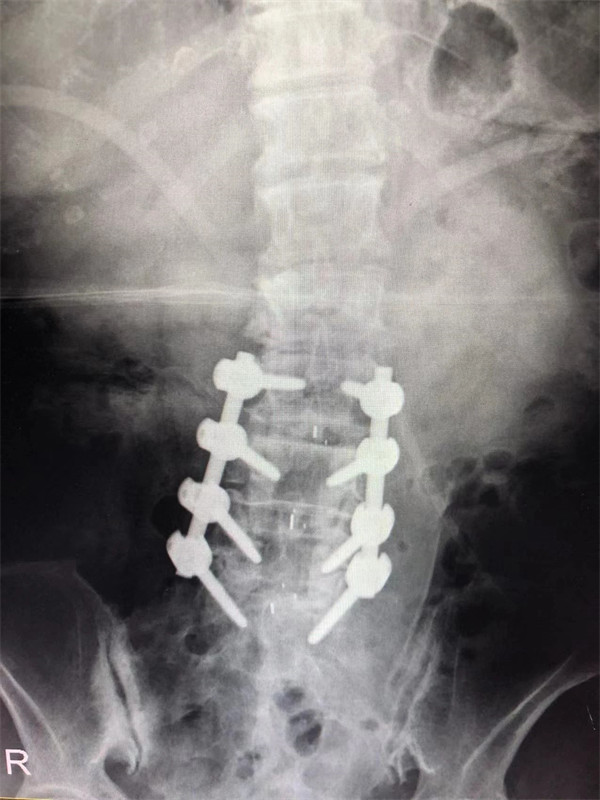

手術(shù)后↓

戈才華主任團(tuán)隊討論病情及手術(shù)風(fēng)險,并與麻醉科醫(yī)生多次討論術(shù)中麻醉風(fēng)險,經(jīng)過詳盡周密的布置之后,最終給阿婆在全麻下進(jìn)行腰3/4,4/5,腰5/骶1腰椎椎體間融合術(shù)。

術(shù)后阿婆腰痛伴雙下肢疼痛明顯緩解,術(shù)前疼得晚上睡不著覺的情況不再出現(xiàn)。阿婆和家屬連聲道謝,對醫(yī)生的治療技術(shù)和服務(wù)贊不絕口。